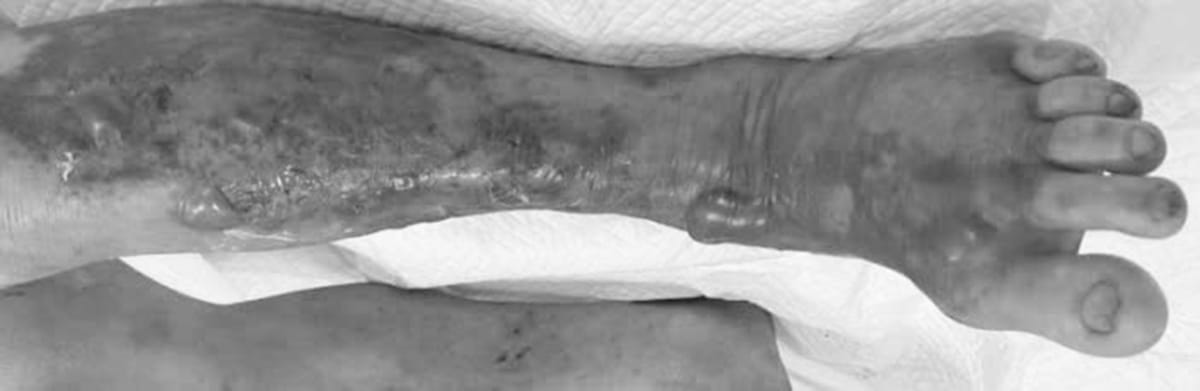

Người bệnh T. 59 tuổi là ngư dân, nhập Viện lâm sàng các bệnh truyền nhiễm (Bệnh viện Trung ương quân đội 108) trong tình trạng tổn thương phỏng nước hoại tử ở da vùng cẳng chân trái, lan nhanh đến đùi, bẹn, tổn thương đa cơ quan (gan, thận). Bệnh tiến triển cấp tính trong vòng 1 - 2 ngày. Người bệnh được điều trị tích cực, làm các xét nghiệm chẩn đoán và tìm căn nguyên nhiễm khuẩn, cấy dịch tổn thương ở da mô mềm và máu dương tính với Vibrio vulnificus.

Hình ảnh tổn thương của người bệnh T. do nhiễm vi khuẩn ăn thịt người. Ảnh: TLBV

Khi da có vết xước, vết cắt hoặc vết mổ chưa lành tiếp xúc với nước biển nhiễm khuẩn, Vibrio vulnificus có thể thâm nhập vào mô mềm và gây nên nhiễm trùng tiến triển rất nhanh. Trong vòng 12 - 48 giờ, vùng da bị nhiễm trở nên đỏ, sưng, đau, xuất hiện bóng nước màu tím/đen hoặc hoại tử.

Nếu không được điều trị kịp thời, nhiễm trùng lan rộng dẫn đến viêm cân mạc hoại tử (một dạng “nhiễm khuẩn ăn thịt người”), thậm chí xâm nhập vào máu, gây sốc nhiễm khuẩn, suy đa tạng và nguy cơ tử vong cao.

Sau thời gian điều trị tích cực tại Viện lâm sàng các bệnh truyền nhiễm, người bệnh T. đã qua tình trạng nguy kịch, hiện đang được Viện Bỏng quốc gia chăm sóc và phục hồi tổn thương da.